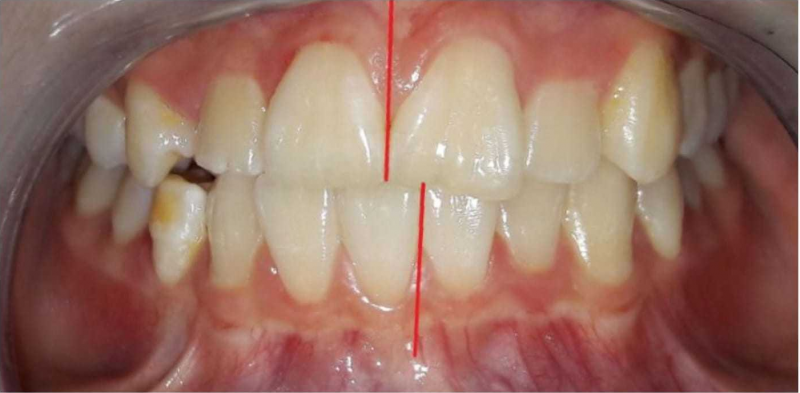

Фотографии до и после: Установка брекетов

На странице представлено портфолио стоматологий Волгограда с фото работ до и после исправления прикуса брекетами. Мы публикуем результаты разных клинических случаев: от скученности зубов и диастем до сложных ортодонтических аномалий. В каждом случае показан реальный прогресс — от начального состояния зубов до финального результата после снятия брекетов и исправления прикуса. Поэтому вы можете наглядно увидеть, как меняется положение зубов и общая эстетика улыбки. Изучите результаты работ до после и выберите подходящую клинику в Волгограде.